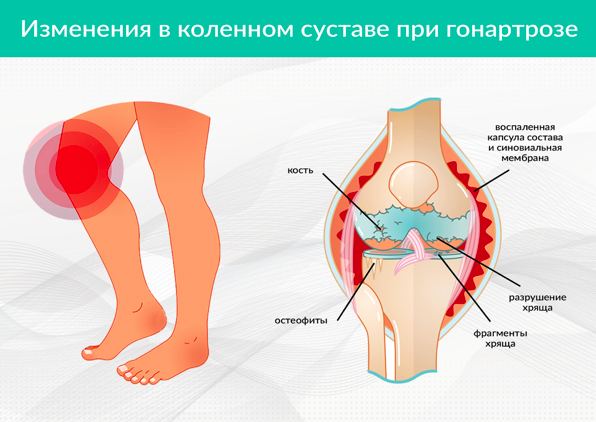

Рисунок 1. Дегенеративный артроз коленного сустава (гонартроз)